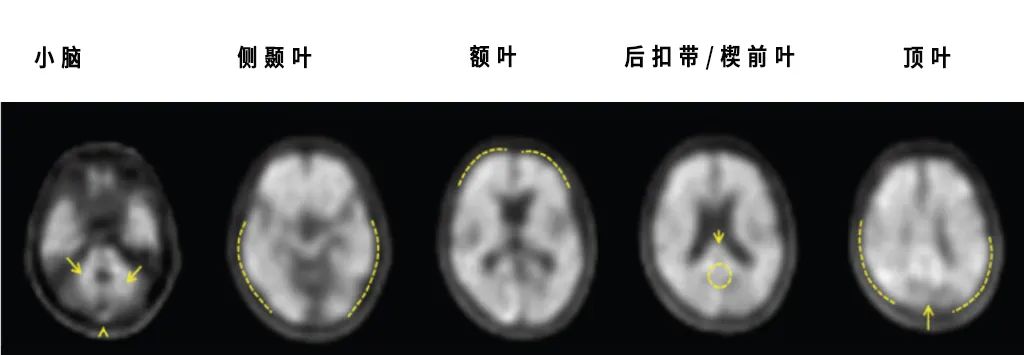

Neuraceq ®扫描图像显示阴性。灰质的显像剂摄取量低于白质,由AD导致认知能力下降的可能性降低

Neuraceq® 扫描图像显示阳性,灰质的显像剂摄取与白质相同或更高,β-淀粉样神经性斑块中度至频繁

▲(通过大脑不同区域对Neuraceq® 的摄取程度来估计β-淀粉样神经性斑块密度,图源:LMI官网)